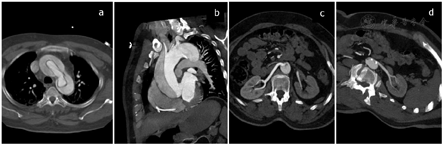

CTA图像显示:主动脉根部至双侧髂总动脉管腔呈双腔样改变(图a~b);两腔密度不一致,假腔大于真腔(图c~d),右侧髂总动脉、髂内外动脉显影明显差;腹腔干受累,显影差(图e~f)。

Ⅰ型主动脉夹层,夹层范围上自主动脉根部下至右侧髂内外动脉、左侧髂总动脉起始部,夹层累及右冠状动脉、头臂干、左颈总动脉、左锁骨下动脉、腹腔干及左肾动脉;右侧髂总动脉及髂内外动脉大范围受累显影差并血栓形成;左肾显影差。